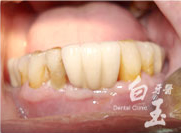

糖尿病嚴重牙周病-王先生

治療前